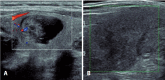

Figures